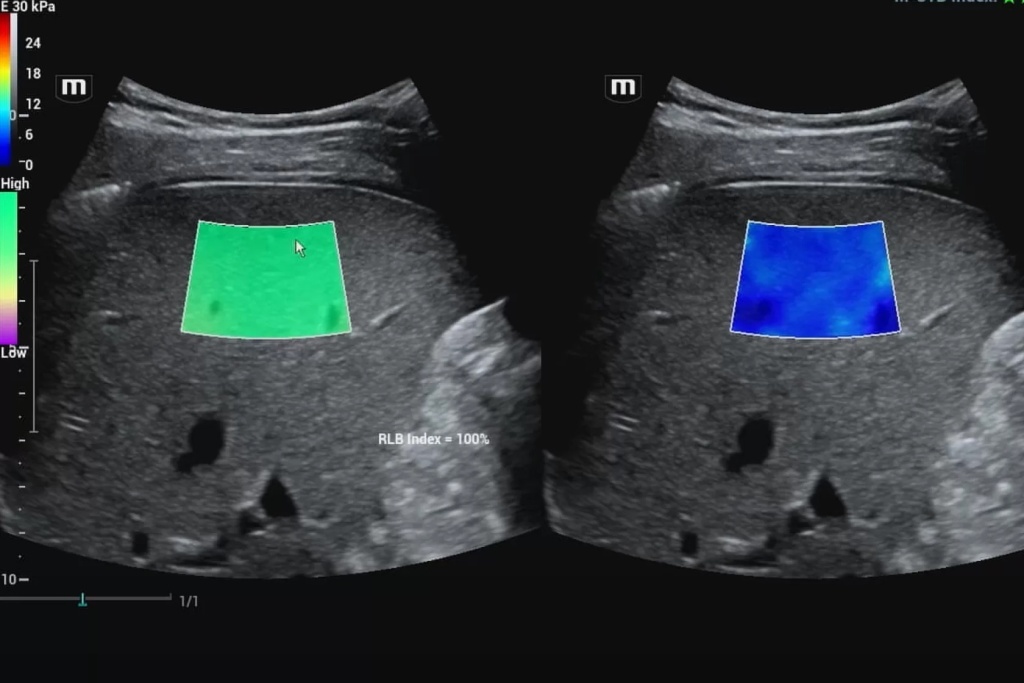

С применением методик эластографии жесткость интересующей нас зоны поверхностно-расположенных и внутренних органов может быть оценена и представлена в виде цветовой эластограммы, наложенной на изображение в В-режиме, и количественно. Это лежит в основе дифференциальной диагностики различных патологических изменений в структуре органа.

В данном случае получение абсолютных значений модуля Юнга (характеризующего жесткость тканей) невозможно, так как его значения зависят от приложенной силы, величина которой не стандартизирована и неизвестна. Поэтому проводится сравнение величины деформации, или стрейна. При воздействии одинаковой силы менее деформируемые ткани являются более жесткими, а более деформируемые – менее жесткими. Ультразвуковой сканер, работающий в специальном режиме, позволяет оценить и сравнить величину деформации тканей в окне опроса и картировать их соответствующим цветом, а также провести полуколичественную оценку – определить отношение деформации в зоне интереса и референсной (условно здоровой) ткани – StrainRatio.

Эластография сдвиговой волной позволяет получить абсолютные значения жесткости исследуемой ткани. В основе данного метода лежит оценка скорости распространения поперечной (боковой) волны, которая может вызываться кратковременным механическим воздействием определенной силы и продолжительности на поверхность тела пациента (это так называемая транзиентная эластография) или сфокусированным усиленным акустическим импульсов в толще исследуемой ткани (именно данные методики в литературе обозначаются как эластография сдвиговой волной). Они в свою очередь подразделяются на методики точечной и двумерной эластографии.